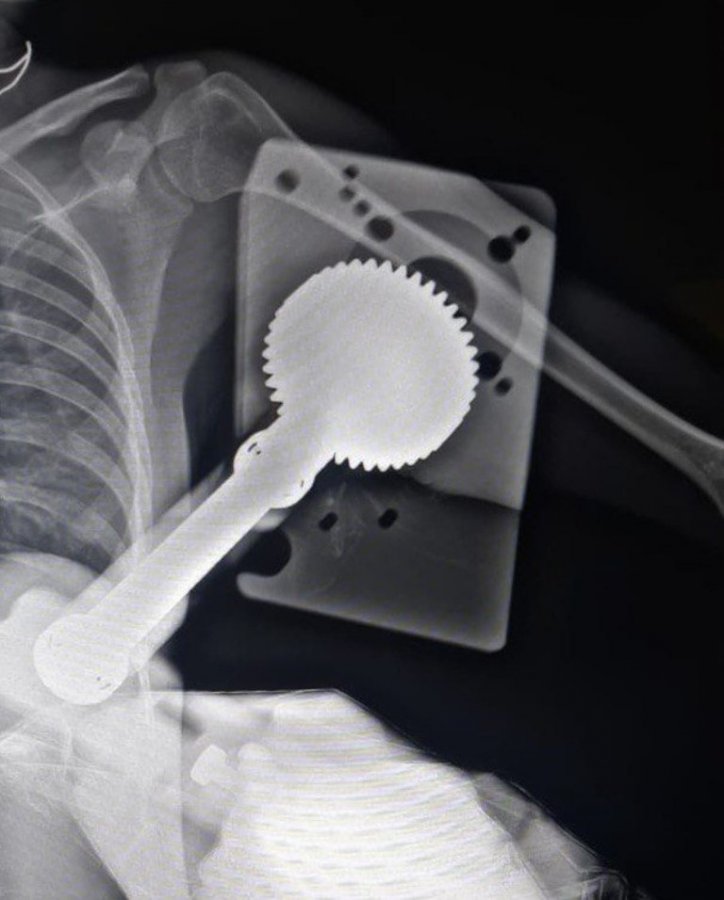

В Каширскую больницу поступила 25-летняя пациентка с обширной раной в области бицепса. В областном Минздраве уточнили, что травму девушка получила, работая с зернодробильной машиной. В какой-то момент ее одежду вместе с рукой затянуло в движущийся механизм, который повредил мягкие ткани и мышцы плеча. Уточняется, что деталь механизма вошла практически до плечевой кости. В экстренном порядке врачи приняли решение провести операцию по спасению руки.

«После хирургической обработки раны мы кропотливо выделили зажатые и поврежденные сосудисто-нервные пучки. После этого извлекли механизм, сшили мышцы и провели пластику дефекта кожи. Магистральные сосуды и нервы оказались не повреждены. Операция прошла успешно и заняла час», – рассказал заведующий травматологическим отделением Константин Смирнов.